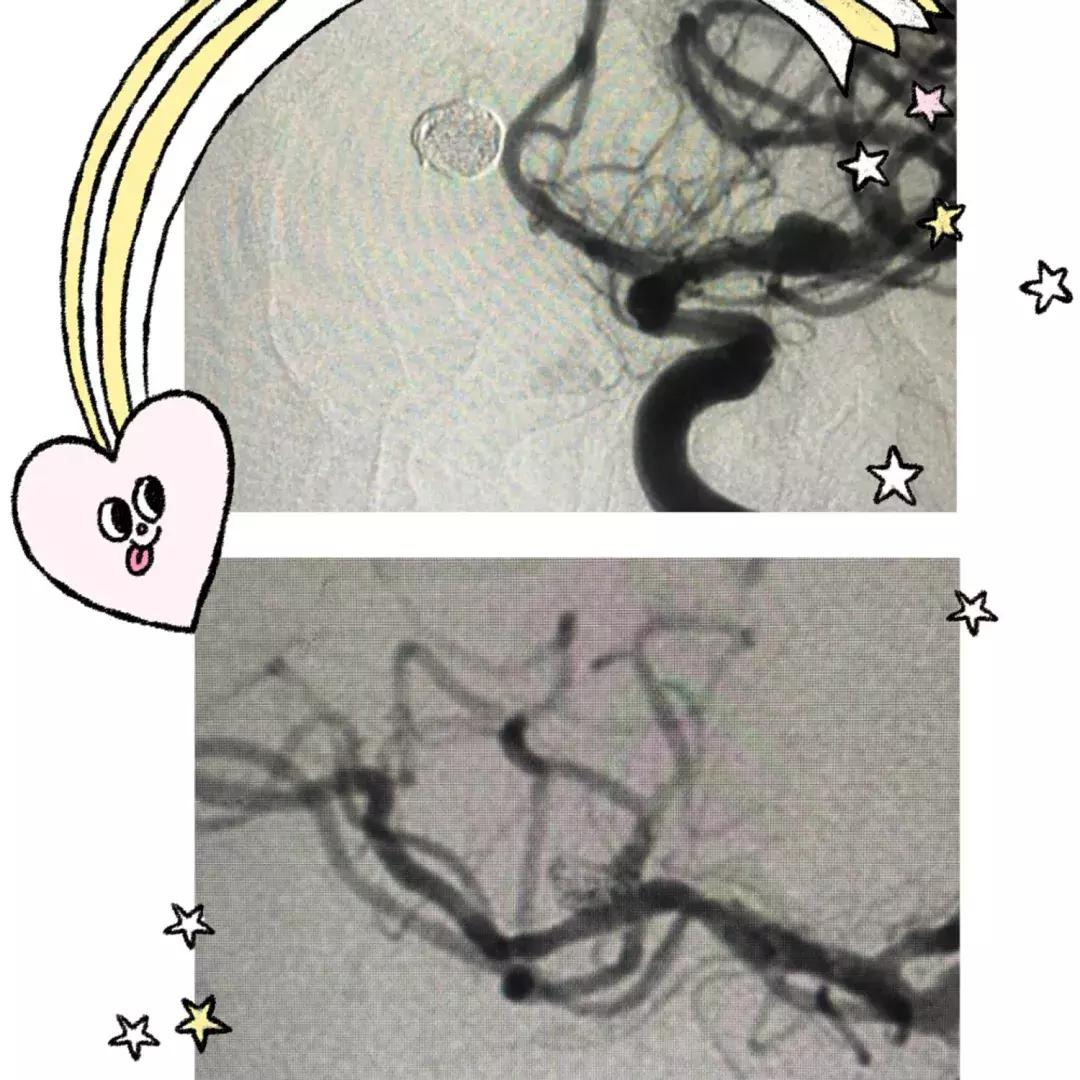

左侧大脑前动脉前交通动脉瘤,瘤颈8.1mm,瘤体8.1mmx3.3mm,右侧大脑中动脉上下干分叉处动脉瘤,瘤颈5.1mm,瘤体5.1mmx4.7mm毫米。均在路图导引下,经支架导管引入支架至动脉瘤颈处,支架半释放,在导丝配合下,将微导管送入动脉瘤腔内,撤出微导丝,依次填塞弹簧圈至瘤腔腔内,完全释放支架,术后反复造影,提示动脉瘤栓塞致密,无造影剂滞留。该次手术一次性解决了两个瘤体破裂的风险!

该病例手术的难度及风险极高,对术者技术水平要求较高,神经内科一病区介入手术团队在常红娟院长带领下,消除了这枚不定时*弹炸**潜在的风险,提高了患者的生活质量。